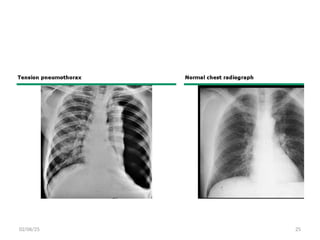

• Tension: This is a surgical emergency

associated with development of pressure

which compromise breathing as well as

circulation.

• Simple: This is collection which is not

associated with compromised breathing and

no breach of chest wall